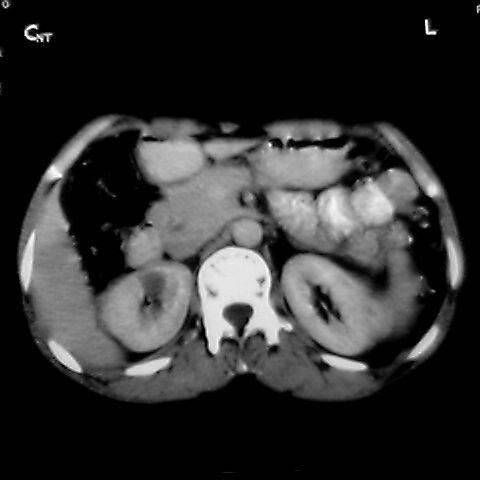

女 48岁 食道癌术前体检发现脾占位。

脾胀内部巨大低密度肿块,边界清或不清,中心坏死,轻度增强,内见散在钙化,结合食道癌病史多考虑:转移癌.

脾脏低密度灶伴钙化,增强化明显,中心见液化坏死灶,强化延时明显。考虑血管瘤。转移瘤待排。

右肾见类圆形低密度影.结合病史.脾及右肾转移性ca可能性大